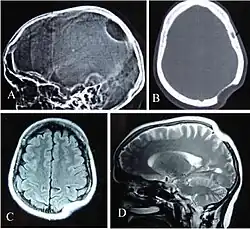

Radiographie du crâne vue latérale (A) montrant une zone ostéolytique dans la région pariétale gauche. CT scan fenêtre osseuse (B), IRM T1W Axiale (C) et T2W Sagittale (D) révélant une anomalie du crâne avec un parenchyme cérébral normal.